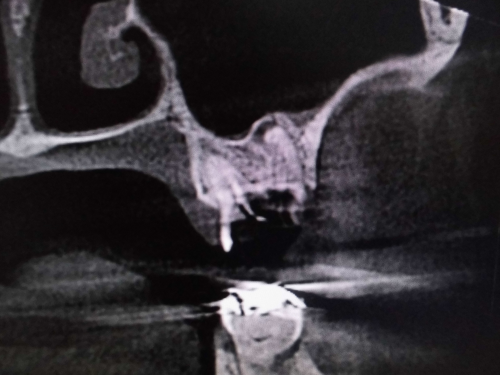

原因が頬側近心根とわかりました。上顎洞粘膜が肥厚しているのもわかります。